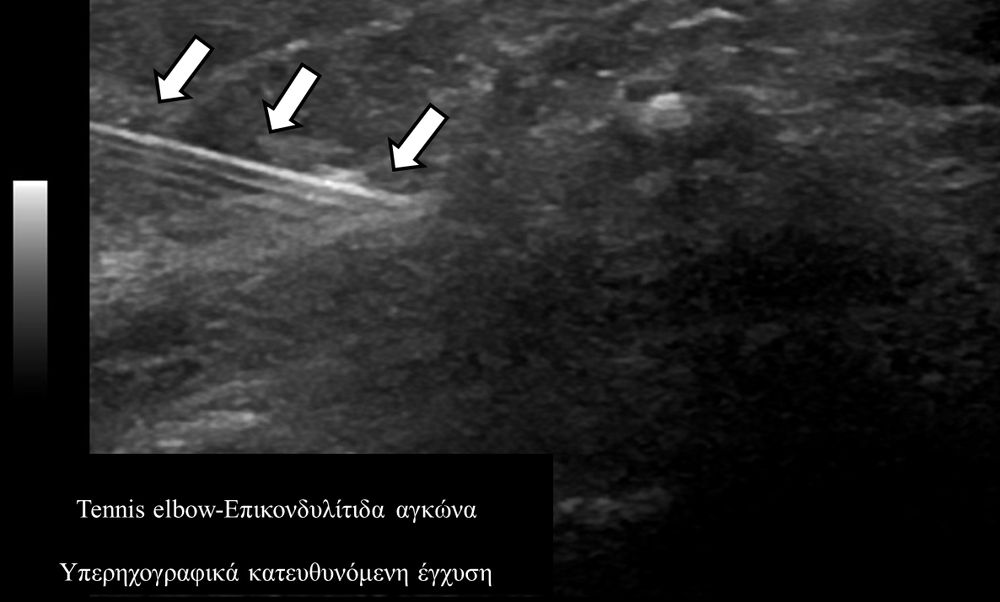

Υπό συνεχή υπερηχογραφική παρακολούθηση είναι δυνατόν να πραγματοποιηθούν κατευθυνόμενες εγχύσεις σε ορθοπαιδικές και ρευματολογικές παθήσεις. Αρχικά εντοπίζεται η παθολογική περιοχή και στη συνέχεια εξετάζεται η βέλτιστη οδός προσπέλασης. Ακολούθως γίνεται υπό άμεση και συνεχή υπερηχογραφική παρακολούθηση οι απαραίτητοι χειρισμοί και έγχυση φαρμάκων ακριβώς στη θέση της βλάβης.

Εχει αποδειχθεί ότι με την υπερηχογραφική καθοδήγηση εξασφαλίζεται:

- μεγαλύτερη ακρίβεια και αποτελεσματικότητα (αφού η έγχυση/θεραπεία γίνεται ακριβώς στηνπαθολογική περιοχή)

- καλύτερη ανοχή από τον ασθενή (λιγότεροι τραυματικοί χειρισμοί αφού έχουμε άμεση και συνεχή εποπτεία της βελόνας)

- μεγαλύτερη ασφάλεια (αποφυγή τρώσης νεύρων, αγγείων, γειτονικών ανατομικών δομών).

σε επικονδυλίτιδα αγκώνα